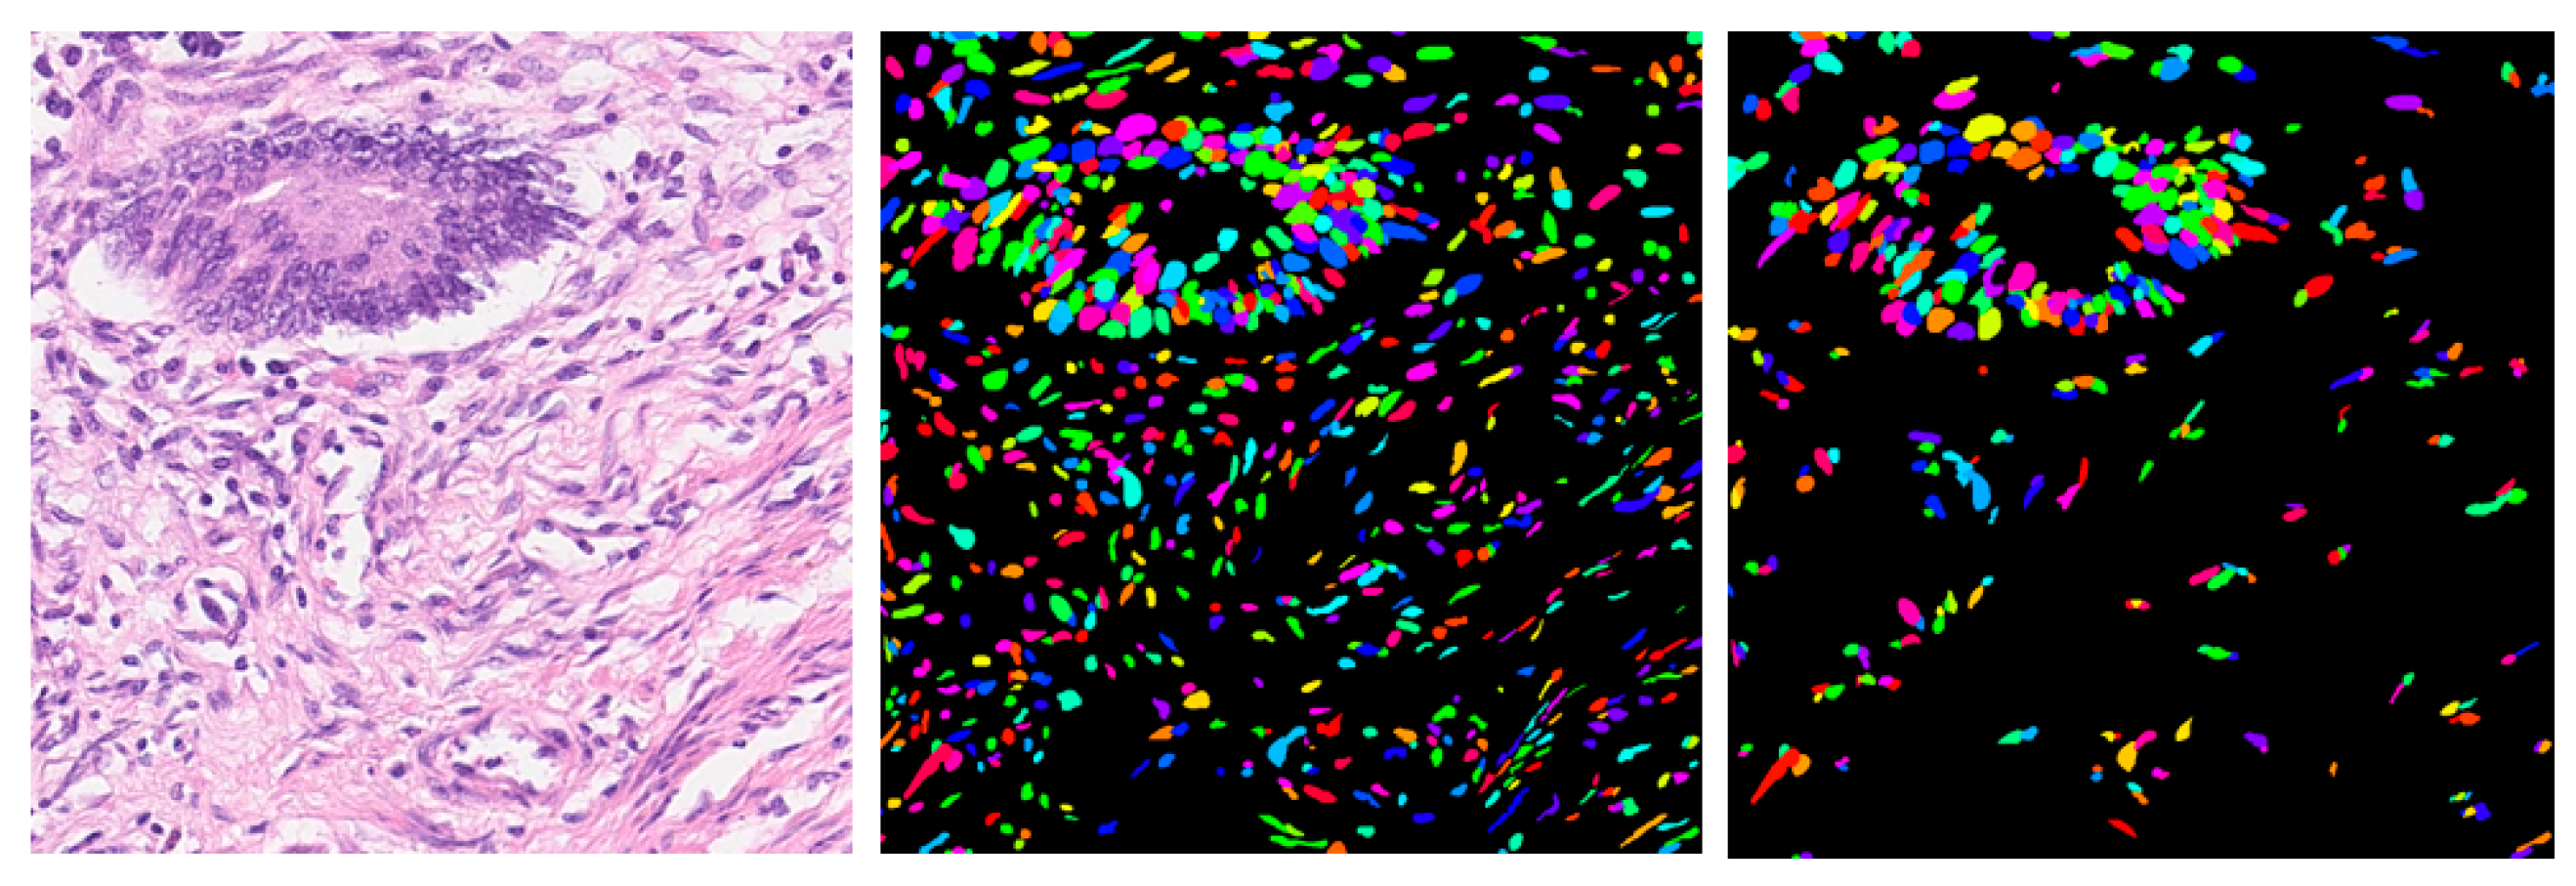

Bend-Net: Bending Loss Regularized Multitask Learning Network for Nuclei Segmentation in Histopathology Images

3. Experimental Results and Discussion